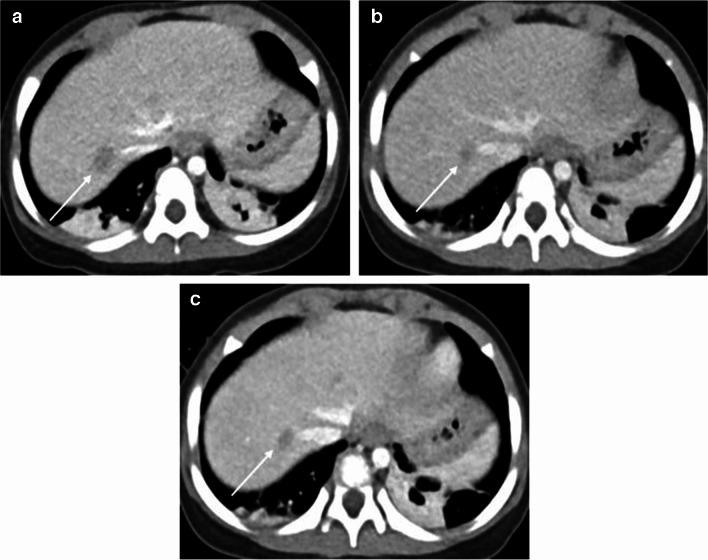

The standard-dose group exhibited higher attenuation, contrast-to-noise ratio (CNR), and signal-to-noise ratio (SNR) of organs and vessels compared to the low-dose group (all P-values < 0.05 except for liver SNR, P = 0.12). However, noise levels did not differ between the standard- and low-dose groups (P = 0.86). The contrast-boosted group had increased attenuation, CNR, and SNR of organs and vessels, and reduced noise compared with the low-dose group (all P < 0.05). The contrast-boosted group showed no differences in attenuation, CNR, and SNR of organs and vessels (all P > 0.05), and lower noise (P = 0.002), than the standard-dose group. In qualitative analysis, the contrast-boosted group did not differ regarding vessel enhancement and lesion conspicuity (P > 0.05) but had lower noise (P < 0.05) and higher organ enhancement and artifacts (all P < 0.05) than the standard-dose group. While iodine uptake was significantly reduced in low-iodine-dose CT (P < 0.001), there was no difference in radiation dose between standard- and low-iodine-dose CT (all P > 0.05).

Low-iodine-dose abdominal CT, combined with an AI-based contrast-boosting technique exhibited comparable organ and vessel enhancement, as well as lesion conspicuity compared to standard-iodine-dose CT in children. Moreover, image noise decreased in the contrast-boosted group, albeit with an increase in artifacts.

与低剂量组相比,标准剂量组器官和血管的衰减、对比噪声比(CNR)和信噪比(SNR)更高(除肝脏SNR外,所有P值均<0.05,肝脏SNR的P值=0.12)。然而,标准剂量组和低剂量组之间的噪声水平没有差异(P=0.86)。与低剂量组相比,造影剂增强组器官和血管的衰减、CNR和SNR增加,噪声降低(所有P<0.05)。造影剂增强组与标准剂量组相比,器官和血管的衰减、CNR和SNR无差异(所有P>0.05),但噪声更低(P=0.002)。在定性分析中,造影剂增强组在血管强化和病变清晰度方面无差异(P>0.05),但与标准剂量组相比,噪声更低(P<0.05),器官强化和伪影更高(所有P<0.05)。虽然低碘剂量CT中的碘摄取显著降低(P<0.001),但标准碘剂量CT和低碘剂量CT之间的辐射剂量没有差异(所有P>0.05)。

与儿童标准碘剂量CT相比,低碘剂量腹部CT联合基于AI的造影剂增强技术在器官和血管强化以及病变清晰度方面表现相当。此外,造影剂增强组的图像噪声降低,尽管伪影有所增加。